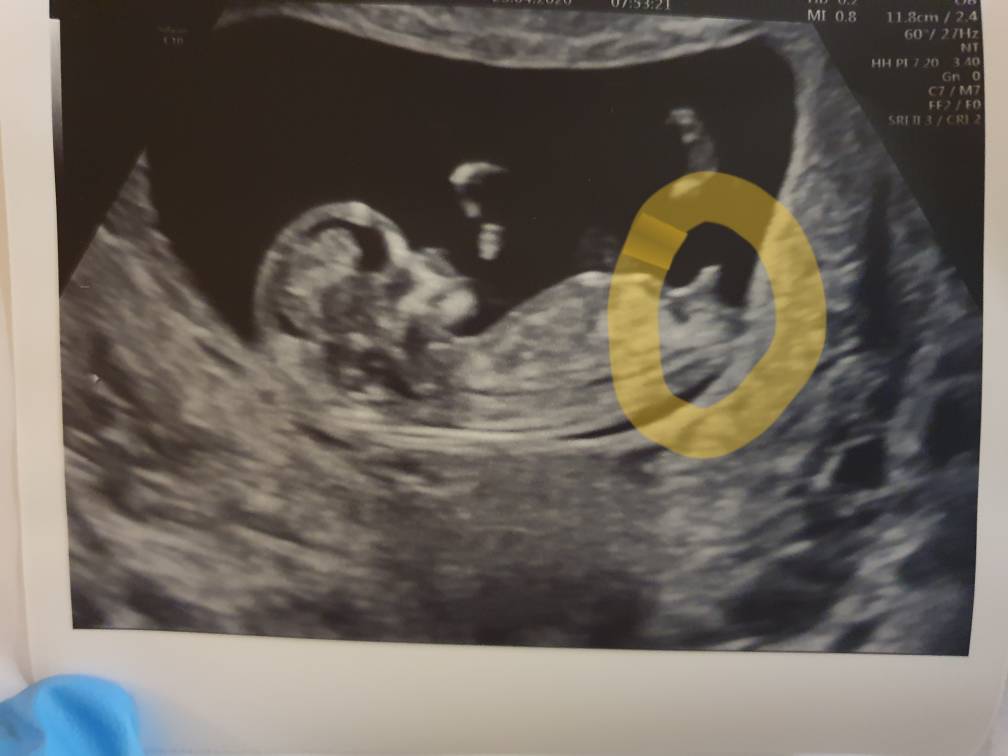

Tym razem gin też zabawił się w odgadywanie płci i jego zdaniem na 90% chlopak [emoji23][emoji23][emoji23]

Jak się fajnie ruszał maluszek [emoji7] pierwszy synek to był śpioch i zawsze na USG odwrócony był pupa i spał :) a tutaj mlodziak brykal [emoji7]

USG zrobil, bo z pomiarów zamiast 11+4 wyszło 12+1 :)

Zobacz załącznik 1109969

Super maleństwo! ❤️ Gratulacje 🌷🌷🌷

Cześć dziewczyny. Chciałabym również wstąpić do grupy zamkniętej. Podczytuje Was praktycznie od początku powstania wątku ale nie miałam odwagi się odezwać. To moja pierwsza ciąża i jestem pełna obaw, w swoim życiu poznałam dużo historii ciąż i niestety w głowie zostają te mało radosne ale... Wczoraj byłam na USG, z mojego wyliczenia i z pierwszego USG był to 11 tydzień i 1 dzień, obawiałam się,że może być za wcześnie ale nie mogłam już wytrzymać. Ku mojemu zdziwieniu z USG wyszło że to 12 tydzień bo maleństwo ma już 5,3 cm. Doktor powiedział,że jak dla niego dziecko ładne, wygląda,że wszystko ok. Kolejny kamień spadł mi z serca [emoji846] dzisiaj idę oddać krew do testu Pappa i kolejne oczekiwanie ehh. Miłego dnia wszystkim życzę.